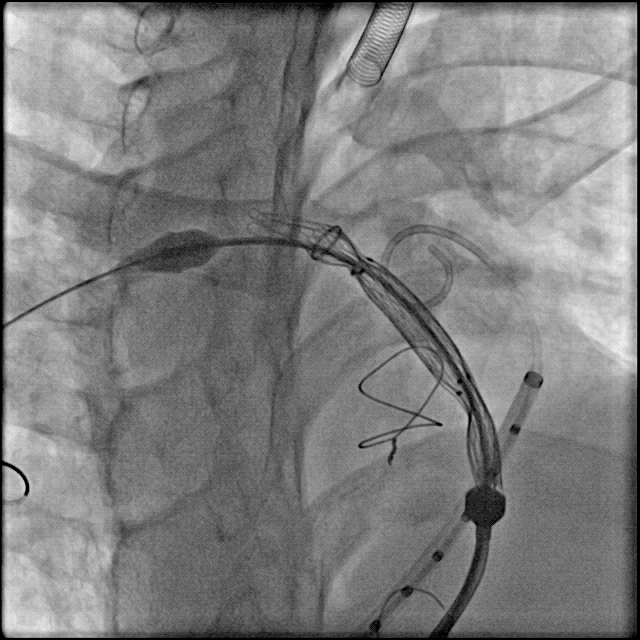

送入输送系统:

根据术前CT、术中造影及球囊测量结果,选择P34-25型号的VenusP-Valve瓣膜,使用圈套器辅助,沿超硬导丝送输送器至肺动脉分叉处。

缓慢释放瓣膜,造影确认人工瓣膜起始位置准确:

继续释放瓣膜,反复造影确认人工瓣膜位置准确:

人工瓣膜释放完成,缓慢退出输送器:

造影确认无明显瓣周漏: